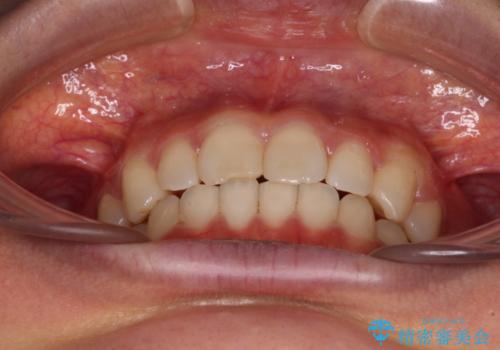

- 近々転勤の予定があるが、早めにインビザラインによる矯正治療を始めたいとのことで来院された患者様です。

上下ともにデコボコの程度は著しいものではなく、インビザラインで十分に対応可能な歯列不正でした。

後戻りによりスペースができてしまうことを避ける目的で、IPR(歯と歯の間を削る)を極力用いない矯正治療を行うこととしました。